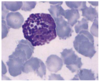

Monocyte 1000x